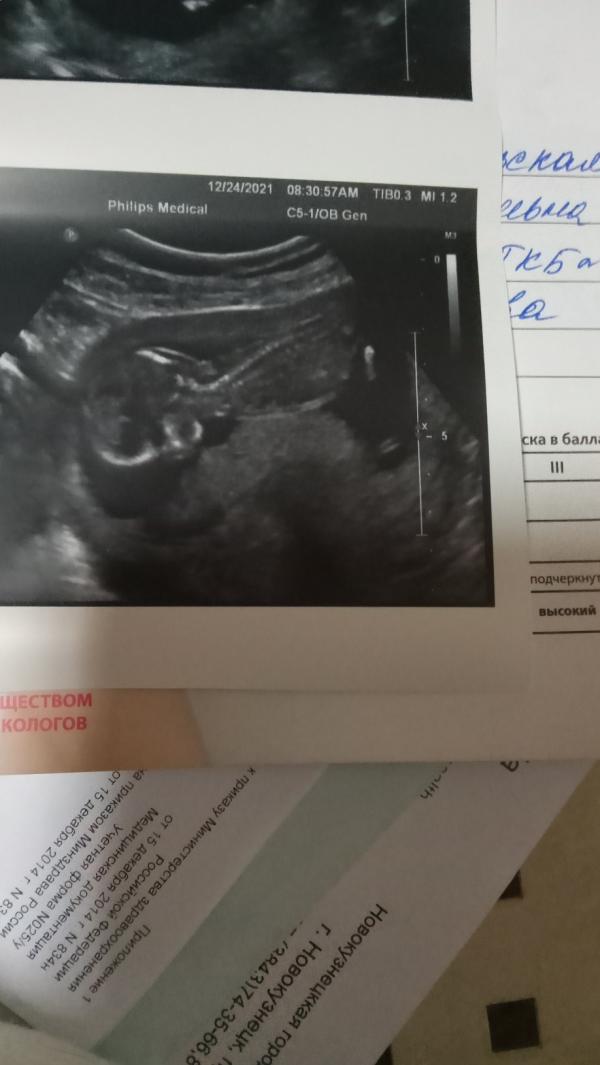

Вчера была на первом скриниге . Там уже настоящий человек прям . Даже экран повернули и показали . Всё без потологий слава богу . Голова , мозг , руки , ноги , туловище , мочевой пузырь , почки , сердце, желудок всё определяется , всё в норме . Рисков нет . Я так переживала , т.к не чувствую ещё шевелений . Но врач успокоил . Сказал бултыхается во всю .